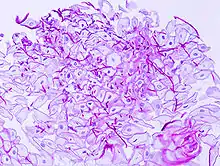

Esophageal candidiasis stained by periodic acid-Schiff procedure

In most cases, the diagnosis is established based on response to therapy. Patients in whom esophageal candidiasis is suspected should receive a brief course of antifungal therapy with fluconazole. If the infection resolves after treatment with fluconazole, then the diagnosis of esophageal candidiasis is made and no further investigation is needed. However, if the infection persists or if there are other factors involved which may warrant further investigation, then patient will undergo an esophagogastroduodenoscopy if it is safe to do so. Endoscopy often reveals classic diffuse raised plaques that characteristically can be removed from the mucosa by the endoscope. Brushing or biopsy of the plaques shows yeast and pseudohyphae by histology that are characteristic of Candida species.